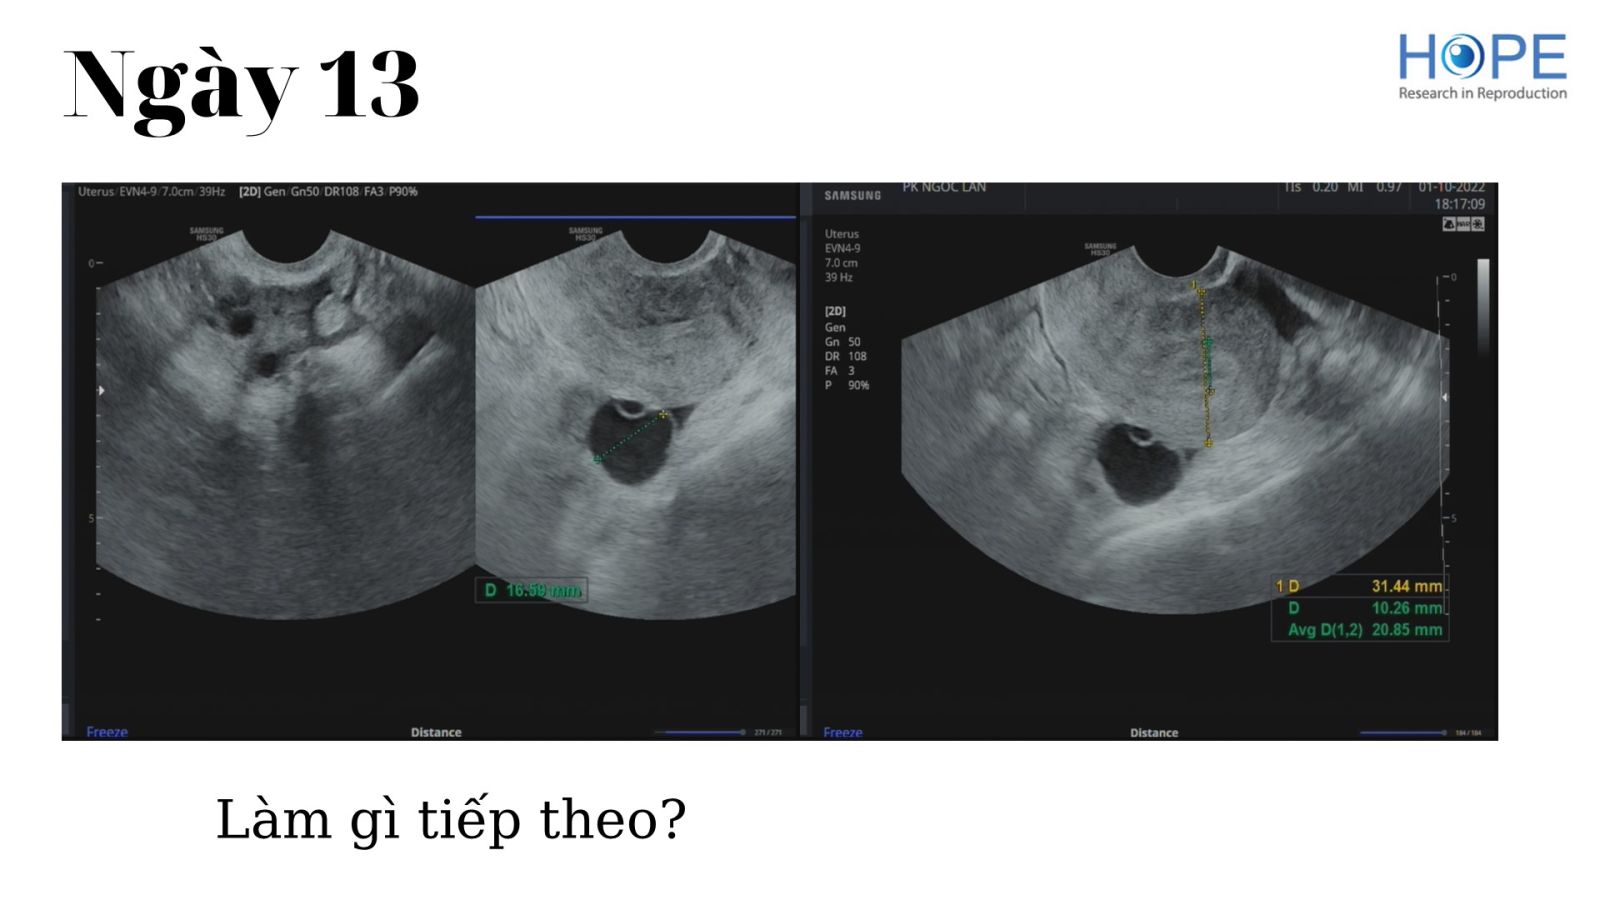

Các phác đồ kích thích buồng trứng nhẹ để IUI –  cách theo dõi kích thích buồng trứng

BS Lê Thị Hà Xuyên - IVFMD Phú Nhuận